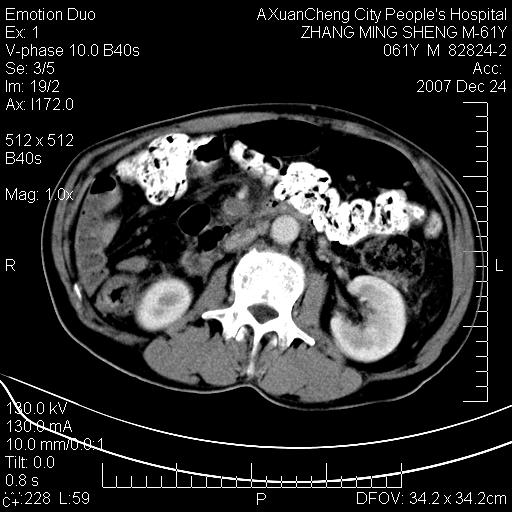

标题: CT11031:M61Y,胰腺占位 [打印本页]

标题: CT11031:M61Y,胰腺占位

大家侃侃门静脉和胆管系统怎么回事,肝内转移?

胰腺癌肝转移

肝硬化,门脉高压,脾肿大;弥漫性肝癌,肝内、门脉、腹膜后淋巴结转移,肝内外胆管扩张,胰头区占位,建议mr检查

胰腺癌伴肝内转移;门脉、肠系膜上v癌栓形成。

考虑为:胰腺癌伴肝脏转移、腹膜后淋巴结转移,门静脉及肠系膜上静脉瘤栓形成。

胰体尾癌伴肝内转移,门静脉及肠系膜上静脉瘤栓形成.

肝硬化,脾大. 胰腺癌伴肝内转移;门脉、肠系膜上v癌栓形成。